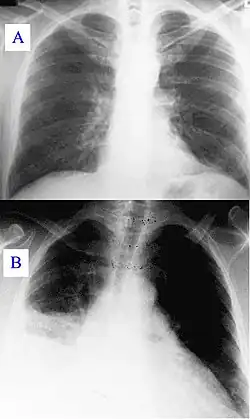

During its course, the disease can progress to an atypical pneumonia, which can result in a life-threatening acute respiratory distress syndrome, usually occurring during the first four to five days of infection.[7]